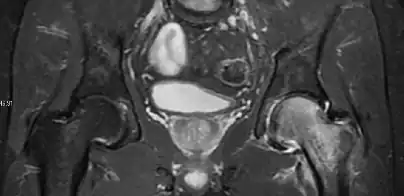

Most of the angles and measurements described in the plain radiograph section can be accurately reproduced on MRI. In addition, the superiority of MRI resolution with intra-articular contrast allows detection of labral and chondral abnormalities that may influence the choice of medical, percutaneous, or surgical management (Figure 9).[1]

Figure 9:

-

Sagittal T1 weighted image showing anterosuperior labral tear.[1] -

Sagittal T1 weighted image showing chondral lesion.[1] -

Sagittal CT-arthrography showing posteroinferior chondral injury.[1] -

Coronal CT-arthrography (d) showing ligamentum teres tear.[1]

MR arthrography has proven superior in accuracy when compared to native MR imaging. It is considered the best technique to assess the labrum. Knowledge of the normal variable morphology of the labrum helps to differentiate tears from normal variants. A triangular shape is most commonly seen in 66% of asymptomatic volunteers, but round, flattened, and absent labra can also be found in asymptomatic populations. MR arthrography has demonstrated sensitivity over 90% and specificity close to 100% in detecting labral tears. Loose bodies are demonstrated as filling defects surrounded by the hyperintense gadolinium.[1]

Association between labral tears and chondral damage has been demonstrated. This underscores the interaction between cartilage and labrum damage in the progression of osteoarthritis. Chondral damage to the posteroinferior part of the acetabulum as a contrecoup lesion occurs in approximately one-third of pincer cases secondary to persistent abutment on the anterior part of the joint leading to a slight posteroinferior subluxation. This is considered a bad prognosis sign.[1]

MR arthrography can also demonstrate ligamentum teres rupture or capsular laxity, which are debated causes of microinstability of the hip. Elongation of the capsule or injury to the iliofemoral ligament or labrum may be secondary to microtrauma in athletes. MR can demonstrate abnormalities in these cases, such as increased joint volume or a ligamentum teres tear (Figure 9).[1]